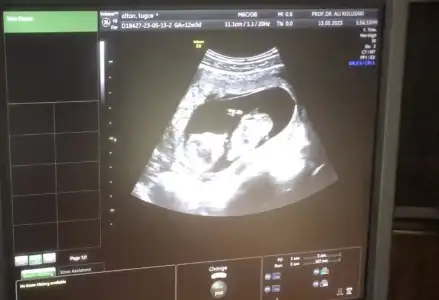

Maşallah minnoşaKızlar ay o kadar heyecanlandım ki başım dönüyordu içeri girdiğimde sanki :)) elleri kolları oynuyordu hareket ediyordu o halini görünce ay o kadar duygulandım ki anlatamamdoktor yüzde 95 kız dedi

böyle bir duygu yaşamadım hiç daha önce ya hala heyecanlayım